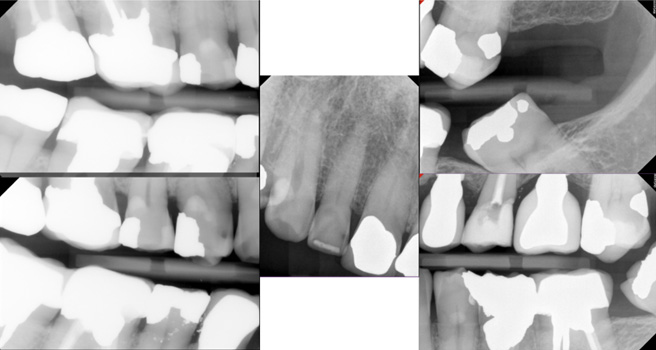

Radiographs

- Radiographs were taken according to As Low As Reasonably Achievable (ALARA) Principles and what was observed clinically. This included 4 bitewing images and 1 anterior periapical image.

Carious Lesions: 12MV, 13DV, 14MOV, 25O, 31V, 42MV, 45V

- Numerous past caries, heavily restored dentition, and current caries (observed clinically and radiographically). In fact, all of his teeth have been restored except for the 36, 41, 47, and 48.

Implant health: Health at implant sites #24 and #26 without bone loss